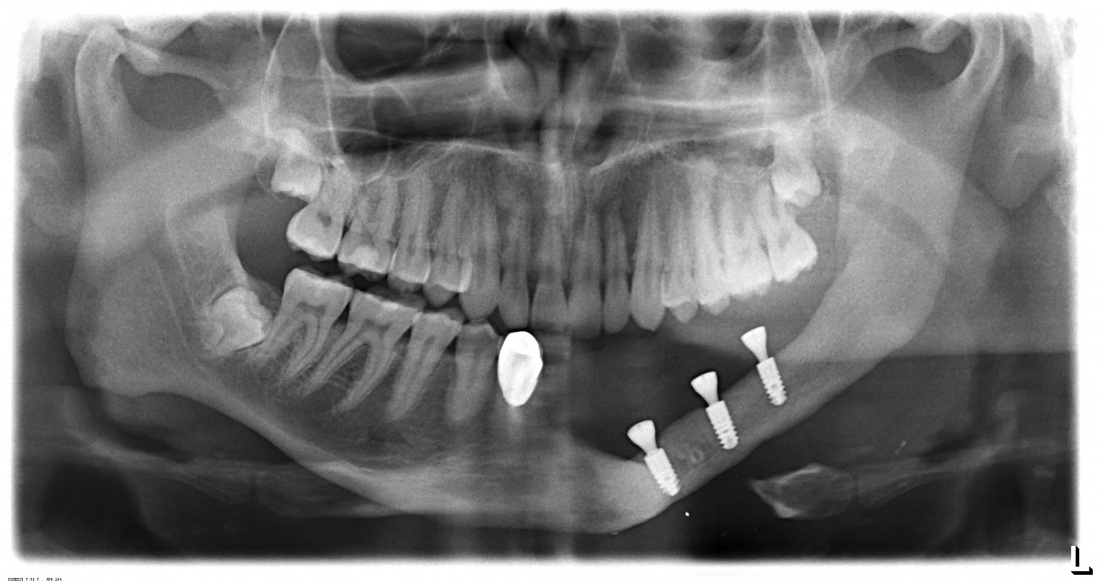

Не нужно расстраиваться! Базальная имплантация — это поправимо.